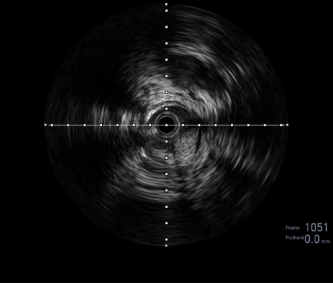

图:IVUS确认

图:Jetstream 应用

图:DCB 5-250 扩张及全程造影